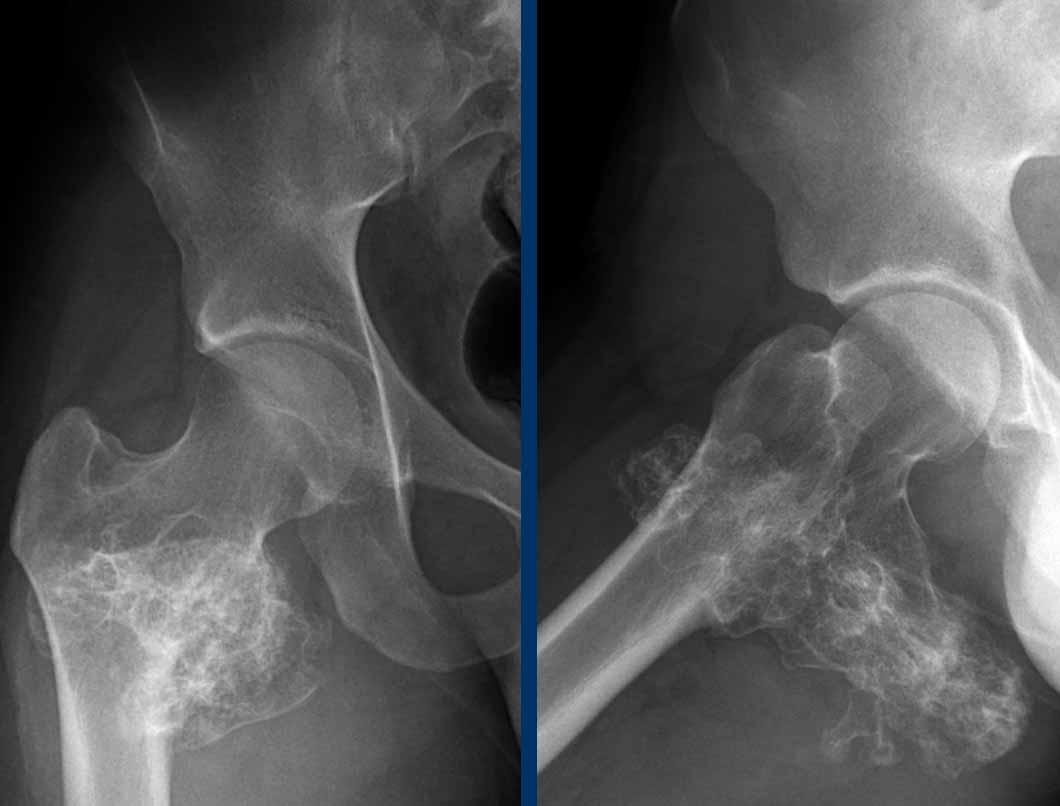

Hình ảnh

Phim X-quang cho thấy một tổn thương tiêu xương dạng giãn rộng xâm lấn ở thân xương đùi đoạn gần của bệnh nhân 30 tuổi.

Có hiện tượng xói mòn vỏ xương lan rộng và phản ứng màng xương dạng gai, kiểu tóc dựng đứng.

Lưu ý gãy xương bệnh lý ở mấu chuyển nhỏ.

Có hiện tượng vôi hóa mờ nhạt trong phần mềm ở phía trong (mũi tên).

Kết luận

Tất cả những phát hiện này đều hướng tới một khối u xương ác tính.

Trong chẩn đoán phân biệt (có tính đến độ tuổi và vị trí thân xương) chúng tôi sẽ bao gồm sarcoma Ewing, nhưng cũng cần xem xét sarcoma sụn độ ác tính cao.

Mặc dù bệnh mô bào tế bào Langerhans cũng có thể xuất hiện ở thân xương dài trong nhóm tuổi này, khối u này rất lớn và phản ứng màng xương quá hung hãn.

MRI xác nhận hình ảnh đa nốt tăng tín hiệu T2 của khối u sụn.

Có một khối mô mềm lớn ở phía trước trong. Có phản ứng màng xương rõ rệt trên MRI, phù tủy xương ở phần gần và phù nề mô mềm xung quanh.

Lưu ý hình thái ngấm thuốc dạng vách-nốt.

Không có ngấm thuốc ở phần trên của khối u và trong khối mô mềm. Đây được coi là thành phần nhầy.

Dựa trên các kết quả MRI, chúng ta nên đưa ra chẩn đoán u sụn ác tính độ II hoặc cao hơn.

Điều trị là cắt bỏ rộng rãi.

Pathology diagnosis: Chondrosarcoma grade III